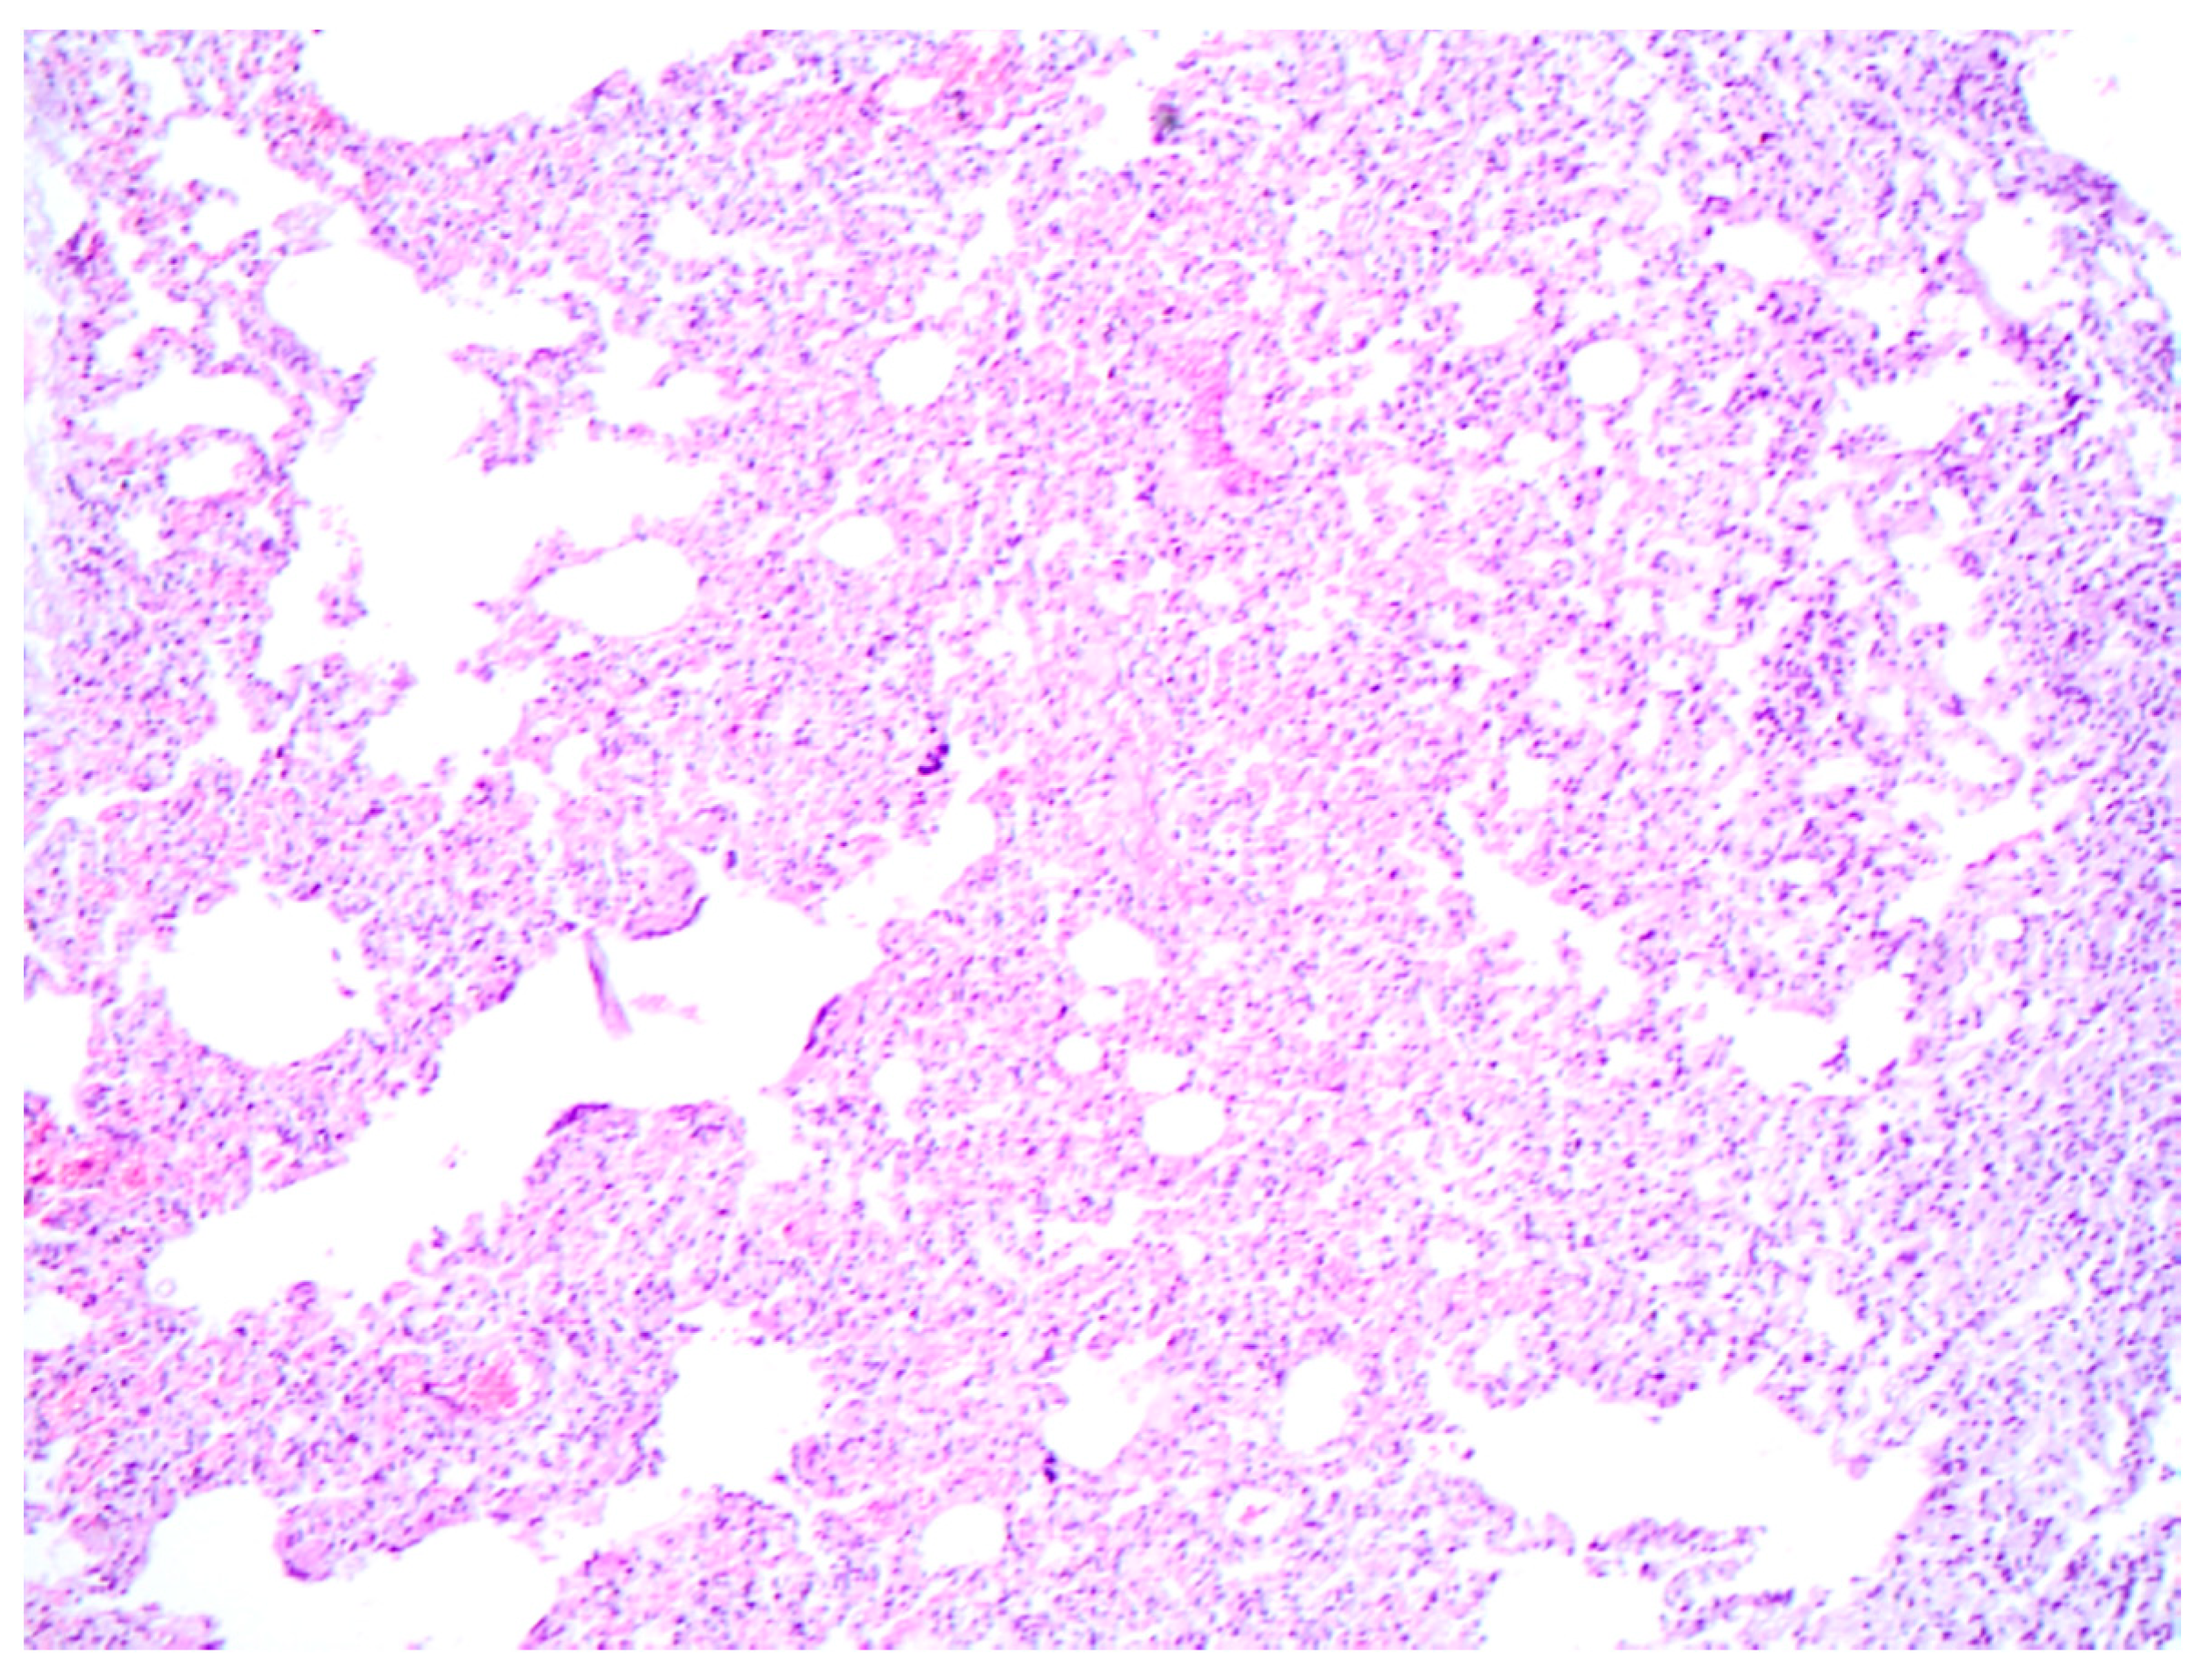

2.3. Histopathology